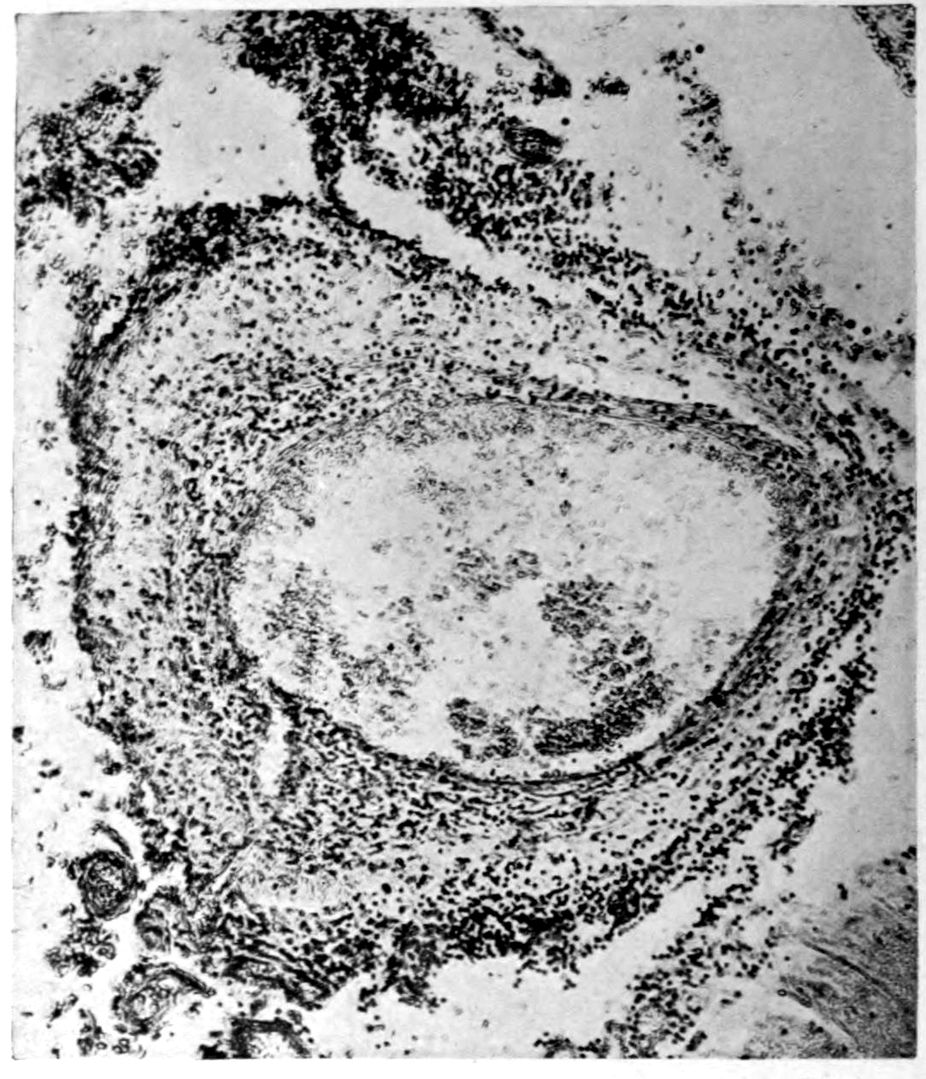

Apparent new formation of small blood vessel. Photographed by Dr. A. M. Barrett.

Rod cells (Stäbchenzellen) in paretic neurosyphilis. Photographed by Dr. A. M. Barrett.

Granular ependymitis—microscopic appearance of a marked example of “sanding” of ventricle.

A. Normal postcentral cortex. (Compare B.)

B. Nerve cell losses. Perivascular deposits of mononuclear cells, amongst which are numerous plasma cells. Note decrease in number of nerve cells. Note irregular disposition of nerve cells. From paretic neurosyphilis.

Microscopic findings are here presented merely in sufficient detail to establish the diagnosis. The left superior frontal gyrus shows extensive and somewhat irregular cellular and fibrillar gliosis of the plexiform layer, together with an increase of thickened vessels having lymphocytes and plasma cells in their sheaths.

The perivascular infiltrations are most extensive in the lower layers of the cortex. The lamination is in places thoroughly obscured, except that representatives of the layer of large external pyramids are almost always demonstrable.

The layer of medium-sized pyramids has undergone more numerical loss of elements than have the other layers.

Gliosis of white matter.

Specimens from the cerebellum show a destructive process of great severity, but a little irregular in extent, affecting chiefly the Purkinje cell belt. The Purkinje cells are often absent throughout one side of a given lamina, and there has ensued a dense accumulation of neuroglia cells along a former Purkinje cell belt, together with a considerable gliosis of the molecular layer. Considerable gliosis of the white matter, both diffuse and perivascular in distribution.

Perivascular plasma cell infiltrations as in cerebrum, but largely meningeal or in the white matter.

Sections from the corpora striata demonstrate a mild and early granular ependymitis, considerable subependymal gliosis of cellular type, considerable perivascular gliosis in the white portions of the tissue, and a moderate infiltration of perivascular sheaths with pigmented cells, lymphocytes, and plasma cells. There is little evidence of alteration in the nerve cells. Some are unevenly pigmented.

41Characteristic and constant in paretic neurosyphilis is the Plasmocytosis and Lymphocytosis, Perivascular in distribution about small cortical vessels. There is also a characteristic (though characteristically less prominent) Plasmocytosis and Lymphocytosis, Meningeal in distribution. The pleocytosis of the spinal fluid, almost constant though variable in amount in life, is an indicator of the meningeal picture and less directly of the parenchymatous picture.

Granular Ependymitis (“sanding” of ventricle floors) is characteristic and may be regarded as part of the parenchymatous picture. This ependymitis is an indicator how chemical changes could be readily produced at least in the ventricular fluids, since the limiting membranes of the nerve tissue are here subject to multiple breaks. The “sanding” is a neuroglia reaction to these multiple small breaks (Weigert’s explanation).